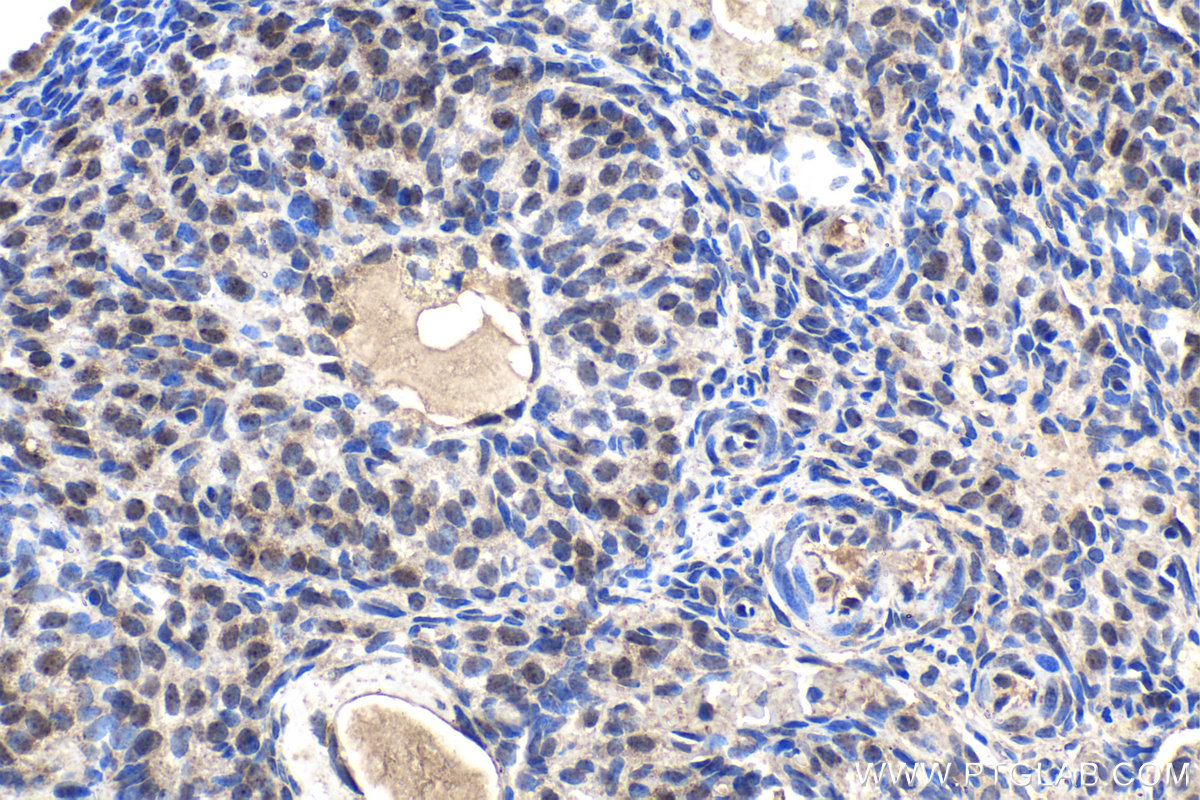

| Positive IHC detected in | rat kidney tissue, human thyroid cancer tissue, mouse kidney tissue, rat ovary tissue Note: suggested antigen retrieval with TE buffer pH 9.0; (*) Alternatively, antigen retrieval may be performed with citrate buffer pH 6.0 |

| Immunohistochemistry (IHC) | IHC : 1:500-1:2000 |